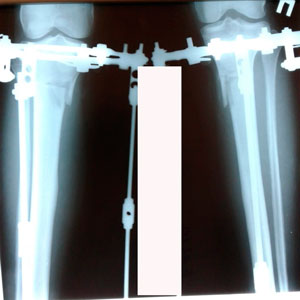

Рентген на фиксации

Вложения

image-11-03-20-11-46-1.jpg

image-11-03-20-11-46.jpg